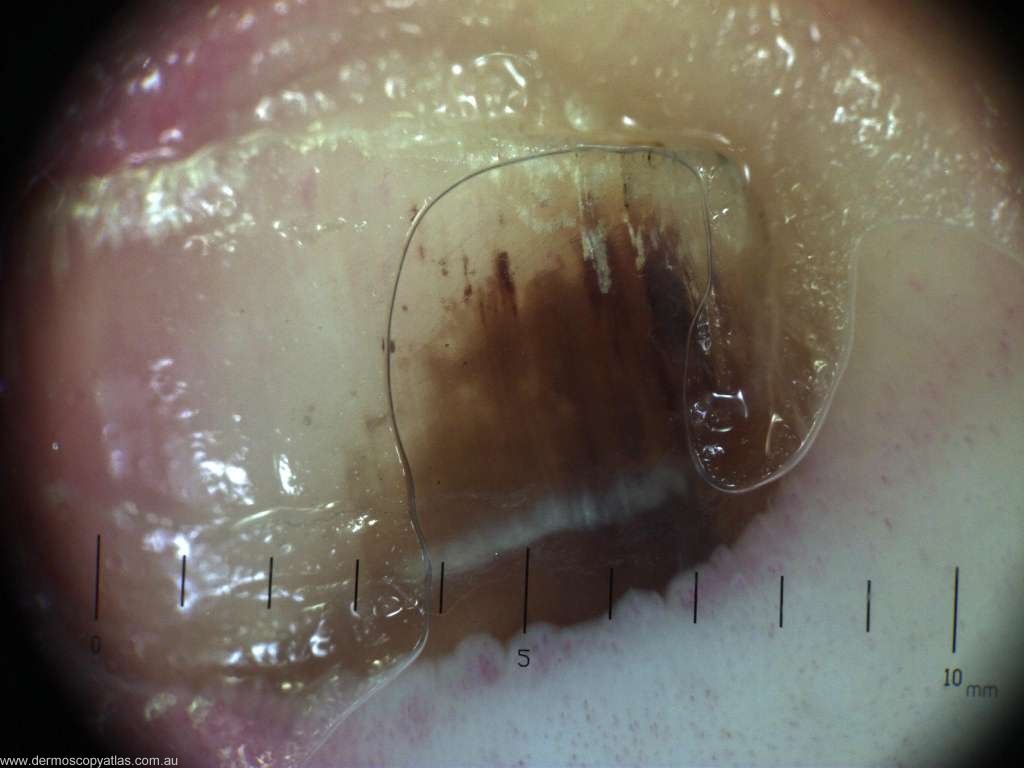

Case 4 45 year old male. Patient aware of nail appearance , but no history of trauma

Question: What do you think the diagnosis is ? Consider Haematoma, Melanoma, Naevus, Onychomycosis and Cheap nail polish.

Answer: Haematoma. (the abnormality resolved spontaneously after 6 months)